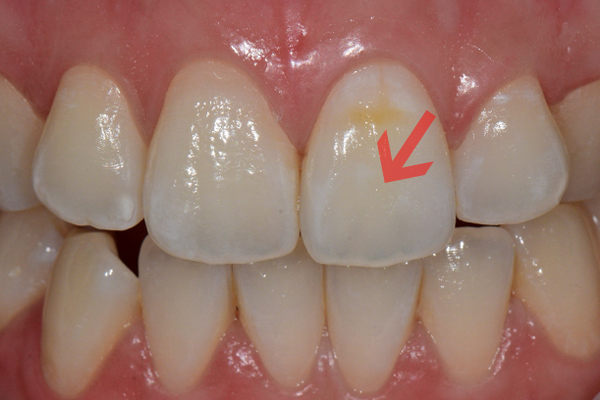

앞니에 생긴 하얀색의 반점을 화이트스팟(white spot)이라고 합니다.

치아의 미네랄 성분이나 구조 변화로 인하여 치아 표면이 주변과는 다르게 빛을 반사하여

말하거나 웃을 때 쉽게 노출되어 심미적인 불편감을 줍니다.

초기 충치의 일환으로 교정 치료 후 발생하는 빈도가 높고 불소 과다 섭취 및 법랑질 저형성증 등으로 나타나기도 합니다.

치료 전